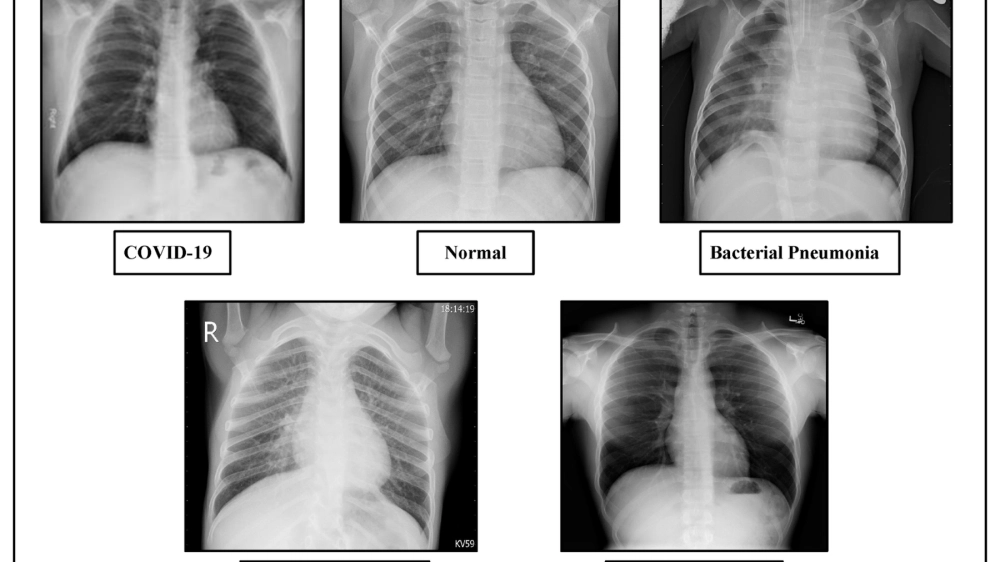

Hình ảnh tổn thương thùy phổi khi chụp X-quang phổi